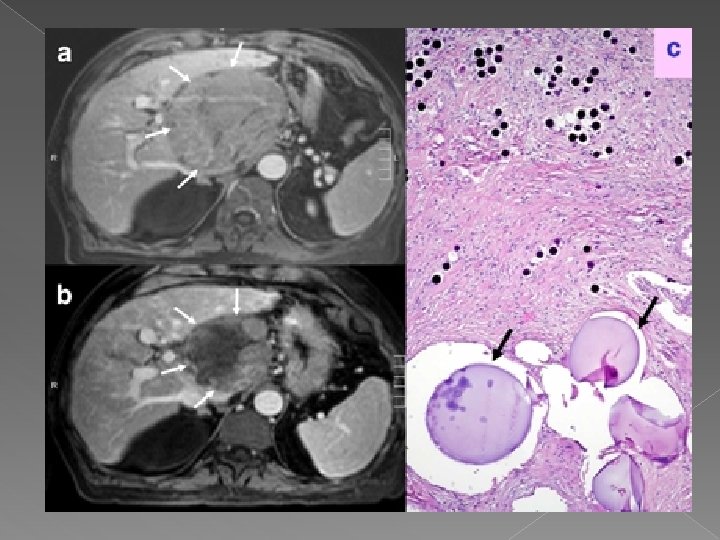

Chiste